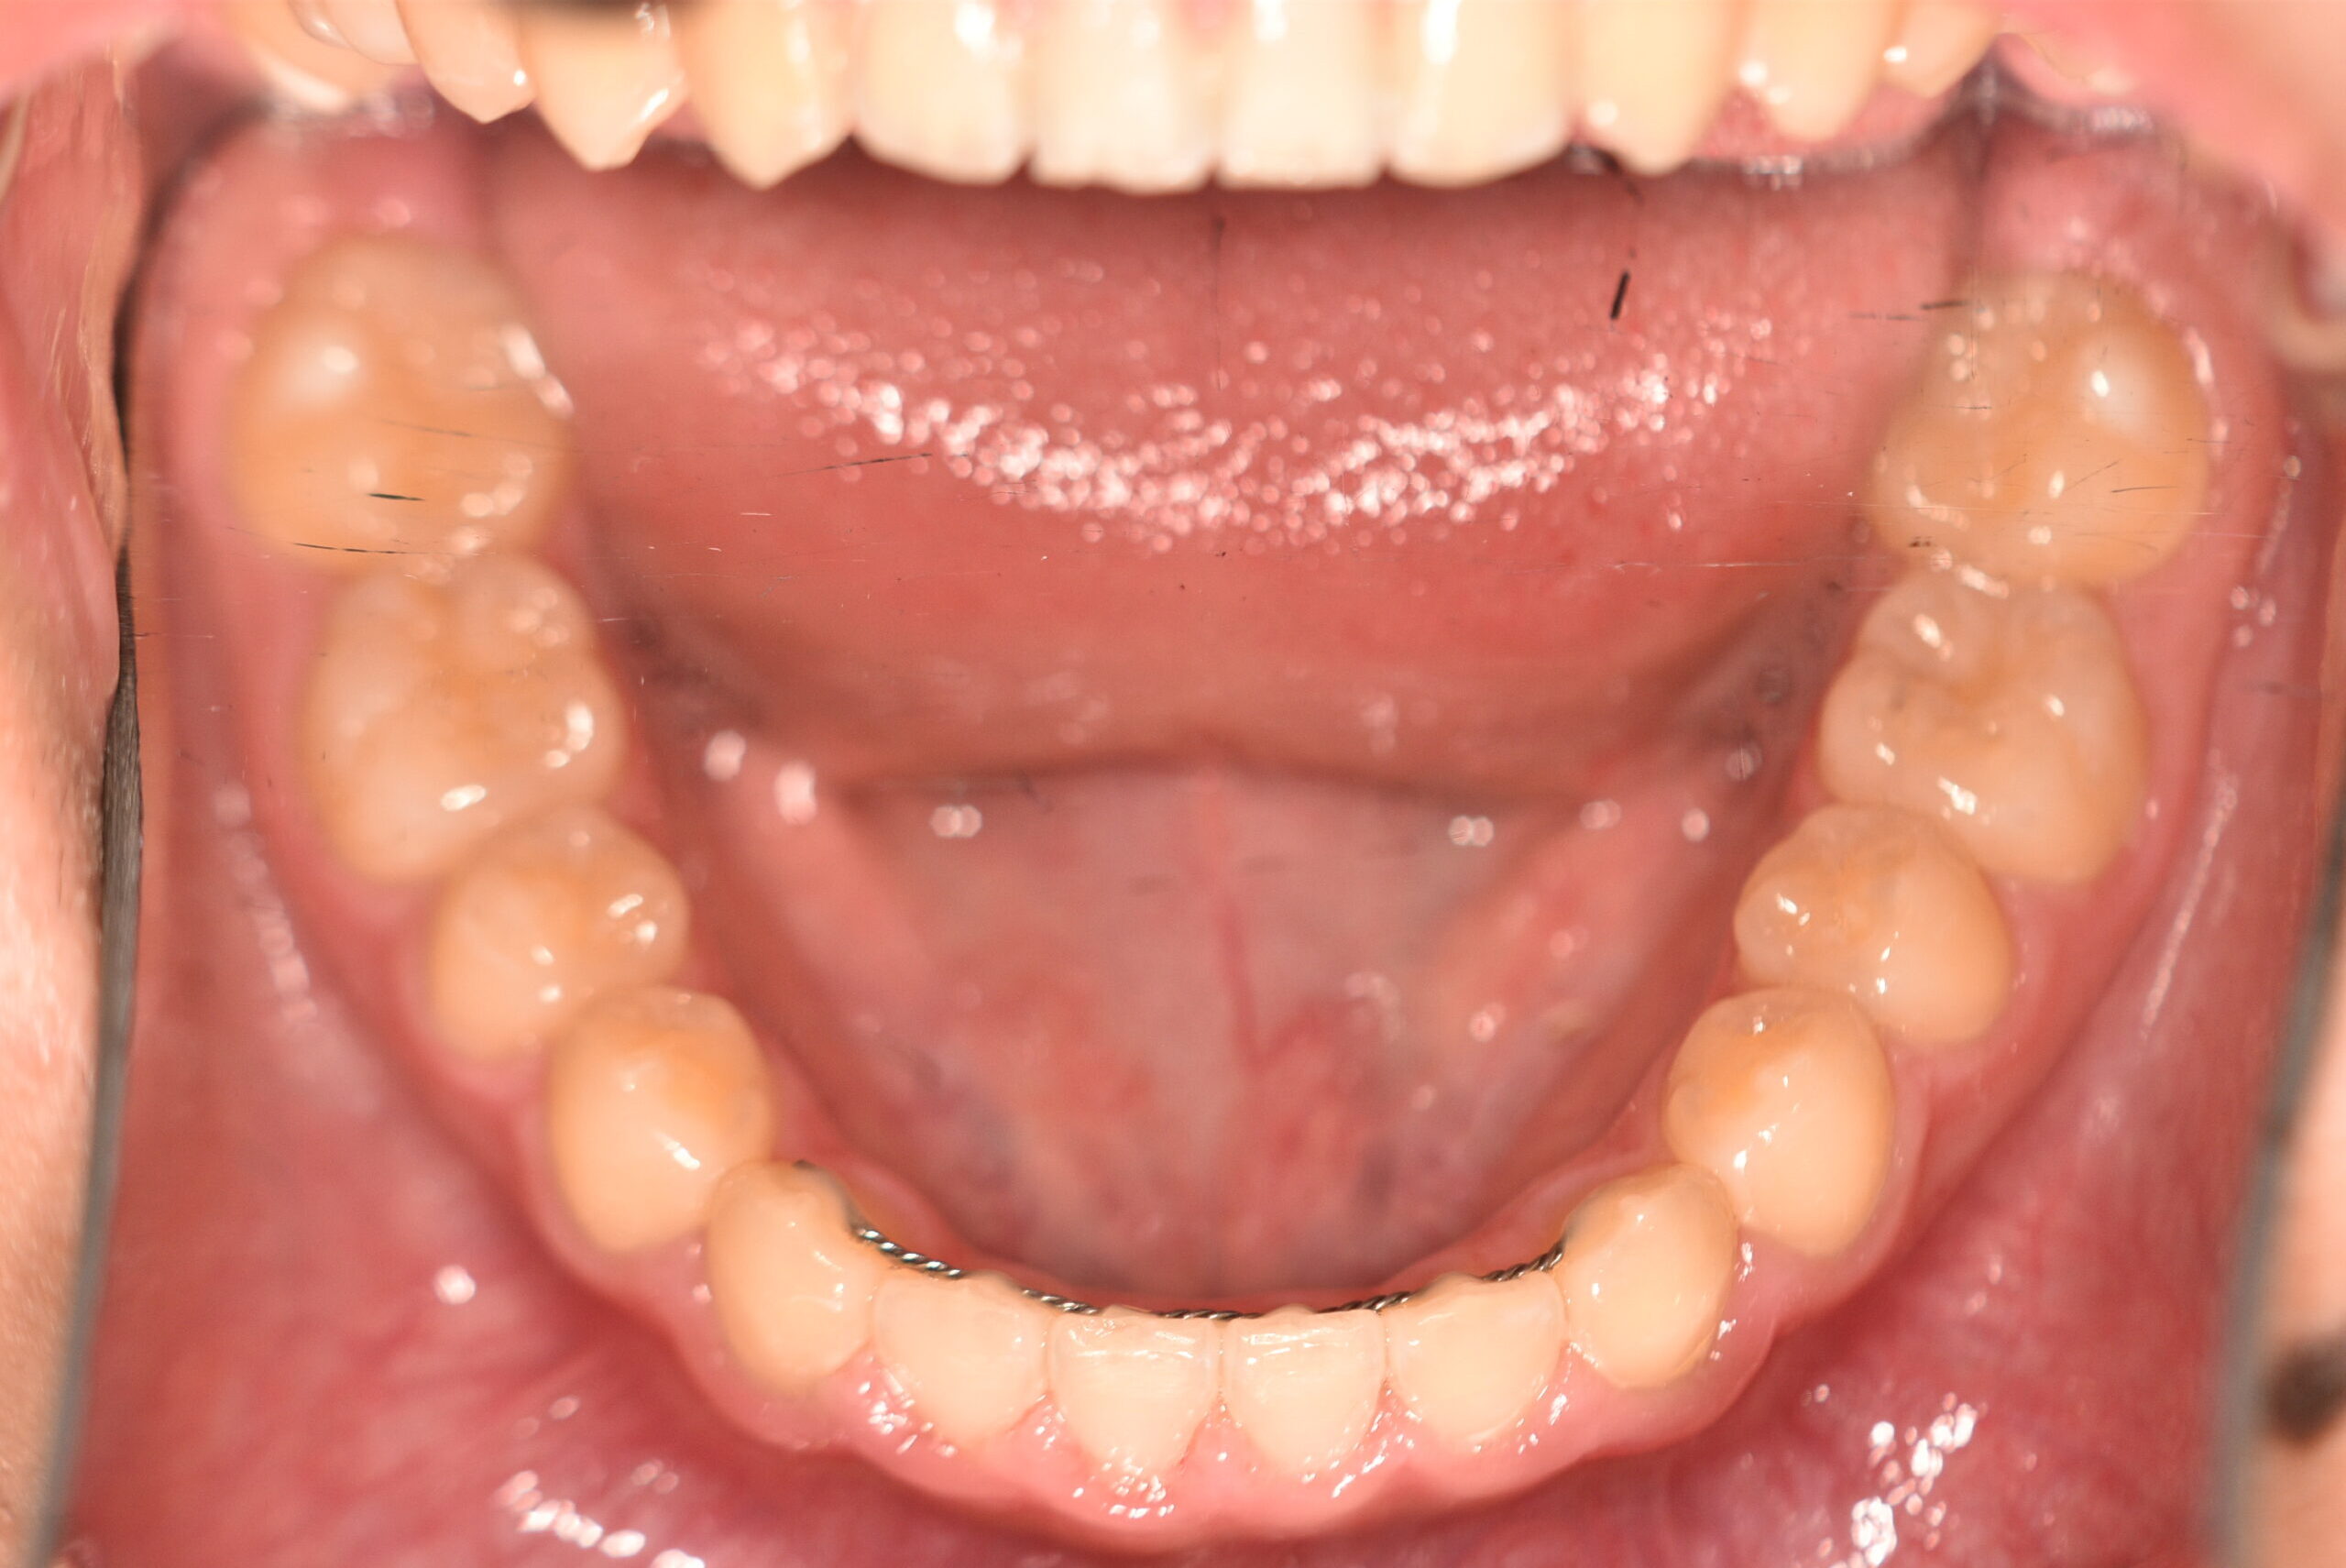

動的治療終了時

症例 症例 症例 症例